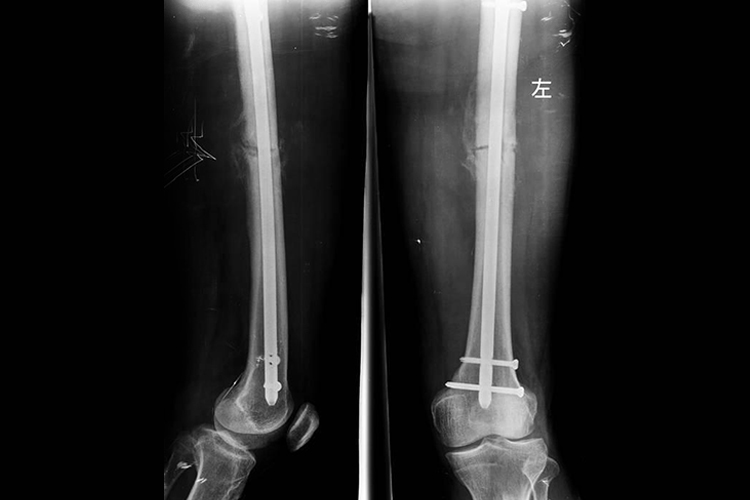

大腿骨干骨折多指股骨骨折,髓内钉固定是利用不同类型的钢钉,穿入需固定的骨干髓腔内,以控制该骨干的骨折位置。一般先将髓内钉安全地装在近端瞄准装置,使用临时透视来确保髓内钉正确地前进穿过骨折部位到达合适位置。在完全打入后,髓内钉的近端应该与梨状窝平齐,髓内钉的远端大约在股骨髁线水平,接近髌骨上极。术后可通过X线检查固定情况。

大腿骨干骨折髓内钉固定适用于病理性、严重粉碎性、节段性骨折。术后患者应注意局部伤口的清洁卫生,注意及时更换敷料,从而预防感染及并发症。同时还应在医生指导下及时进行功能锻炼,如抬高患肢、固定肌肉行等长收缩、关节主动运动及抗阻运动等,从而促进血肿的吸收、加速骨折断端的纤维性连接和骨痂形成、防止关节粘连僵硬、恢复关节活动、防止肌肉萎缩、恢复肌力。